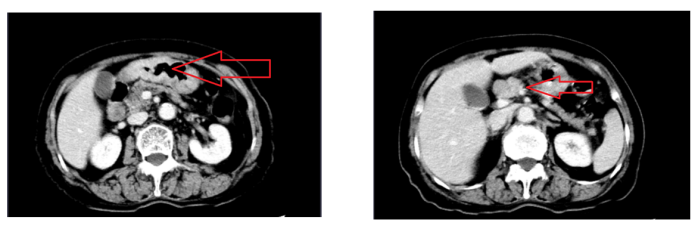

2)2021年7月25日,本院全腹CT平扫+增强(图1)示: 胃体、胃角及胃窦部胃壁多发增厚,增强后黏膜不均匀强化,周围浆膜面稍毛糙,胃癌考虑,伴胃周及小网膜多发淋巴结肿大,部分融合,较大一枚径约3.6cm。

图1 基线全腹CT平扫+增强